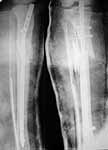

Subject: Unhappy (valgus) tibia nailing

Dear colleagues,

A female 24 years old, a sister of a friend of mine (not physician) living in Moscow, 3 weeks ago admitted to the hospital in Moscow after a car accident (was a pedestrian) with a tibial shaft fracture. 3 days ago closed locked nailing was performed, see attached films. Now he is in panic because they are going to remove the nail and perform plating.

The tibia shaft fracture (proximal 1/3 of the shaft) is apex medial 20 degrees, slightly short and a few degrees apex anterior after nailing. The nail extends quite proximal to the entry site. I wasn't able to see the distal end of the nail on my screen and am not certain if there was distal locking.